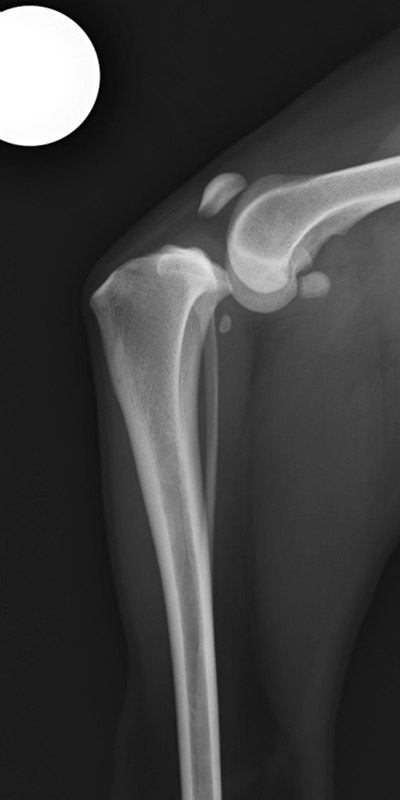

手術前

手術後